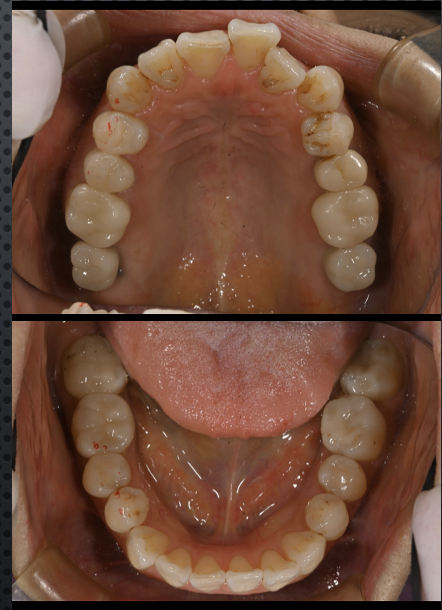

before

after